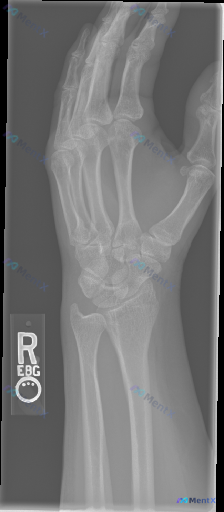

整理到一张右侧(R)腕关节侧位X光片的配套影像分析资料,先把核心客观信息整理出来: 影像基础观察 1. 整体对位:桡腕关节、中腕关节及腕骨序列基本对齐,月骨无明显脱位,未见Colles/Smith骨折典型侧位改变,也未见明确的TFCC间接异常征象; 2. 骨骼完整性:桡骨远端、舟骨、三角骨、头状骨等...

各位同道,今天分享一张手部侧位X光片。影像所见:手部呈屈曲(握拳)位投照,掌骨(第2-5掌骨)及指骨(近节、中节、远节)形态大致完整,骨结构尚连续,骨小梁纹理清晰,骨密度未见明显异常增高或减低,未见明显皮质连续性中断、骨折线或透亮线,未见明显溶骨性或成骨性病变征象;掌指关节、指间关节对位关系可见,关...